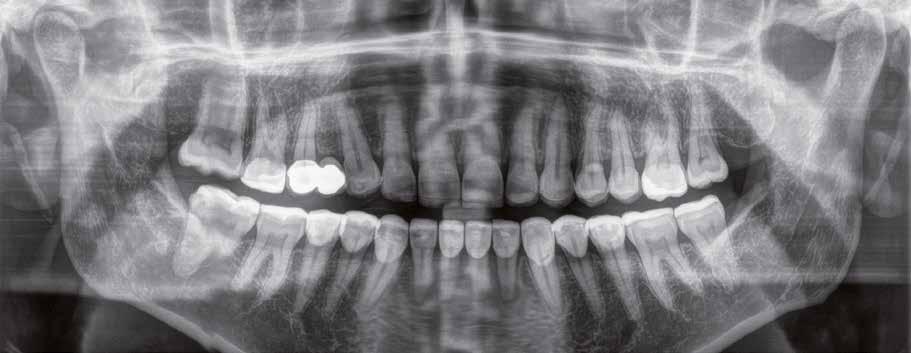

Panorámaröntgen elemzése mesterséges intelligencia által.